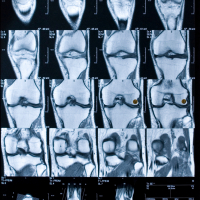

MRT vom Knie

• Wenn das Knie schmerzt -  Eine systematische Übersichtsarbeit von Cochrane aus dem Jahr 2022 beschäftigt sich mit der Frage, ob ein verschleißbedingter Meniskusriss operiert werden sollte.  Birgit Schindler und Cordula Braun von Cochrane Deutschland haben sich den Review für Wissen was Wirkt genauer angesehen. Ihr Fazit: Die verbreitete Intuition , eine OP sei „die beste Wahl“, wird durch die verfügbare Evidenz nicht gestützt.